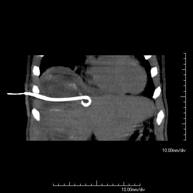

- CT-guided abdominal drainage (abscesses, collections)

It consists of placing a drainage catheter over a collection of fluid located in the abdominal cavity, with the intention of emptying as much of the collection as possible. The patient should keep the drain in place for a few days, usually until it is no longer productive. It is often performed under sedation with the help of an anaesthesia team. The entire procedure is monitored using images obtained by computed tomography (CT) at various stages of the test, using CT fluoroscopy. After the test, the patient remains hospitalised. Coagulation tests must be performed before the test.

- CT-guided abdominal drainage